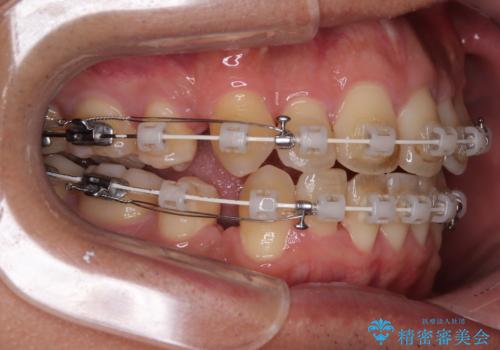

使用した装置は、透明感のあるプラスチックブラケットと白くコーティングされたワイヤー。

金属の装置に比べて目立ちにくく、治療中も自然な見た目を保ちながら矯正を行うことができました。

舌を前に押し出す癖(舌突出癖)があり、後戻りやオープンバイトの再発防止のため、MFT(口腔筋機能療法)も併用しています。